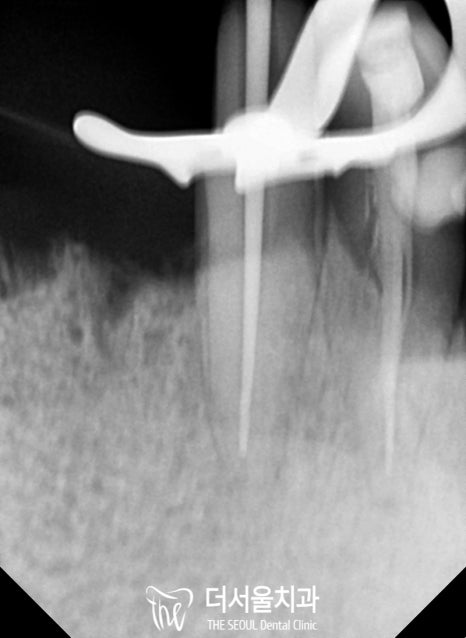

하악 신경치료를 진행한 다음,

오염된 치수를 제거하고 근관의 길이를 측정했습니다.

전치부

이후 소독 과정을 거친 뒤,

뿌리 끝부분부터 빈 공간이 남아있지 않도록

밀봉을 도와드렸습니다.

자, 여기서 Point!

뿌리 끝까지 확실하게 밀봉하는 것이 중요합니다.

이 과정의 결과를 좌우할 수 있는 관건이 되는데요.

만약 뿌리 끝까지 채워지지 않았다?

그러면 또 다른 염증이 생기거나,

같은 곳에 병소가 재발하는 일이 생기게 되죠.

전치부 / 구치부

숨어있는 미세 근관까지 빼곡하게 채워주었습니다.

파노라마 사진을 보면 뿌리 끝까지 채워진 모습을 볼 수 있네요.